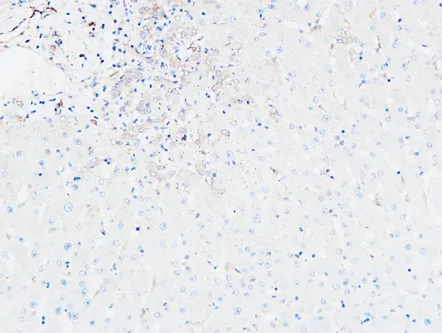

HDC Rabbit Polyclonal Antibody

Cat: APRab11956

Size1:50μl Price1:$118

Size2:100μl Price2:$220

Size3:500μl Price3:$980